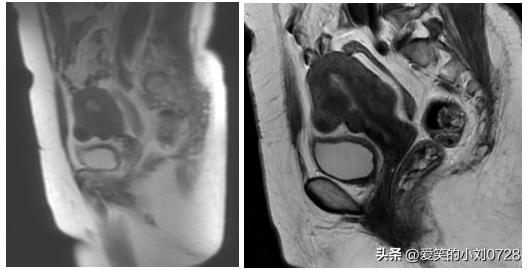

考虑阿姨不能除外子宫内膜癌,我们给阿姨完善了子宫内膜癌相关的辅助检查,比如盆腔核磁(见图1)、CT等,查了肿瘤标志物在正常的范围。

盆腔核磁结果: 肿瘤标志物在正常的范围

因为阿姨在术前已经行全腹的增强MR(核磁共振)评估无盆腔淋巴结肿大,术中冰冻病理提示为局灶癌变,且为高分化。和家属沟通,可以不行盆腔淋巴结清扫,或者行前哨淋巴结活检,阿姨家属要求不行淋巴结清扫术,所以结束手术。手术非常顺利,术后病理出来后也提示是早期的子宫内膜癌,预后较好,不需要进行任何辅助治疗。